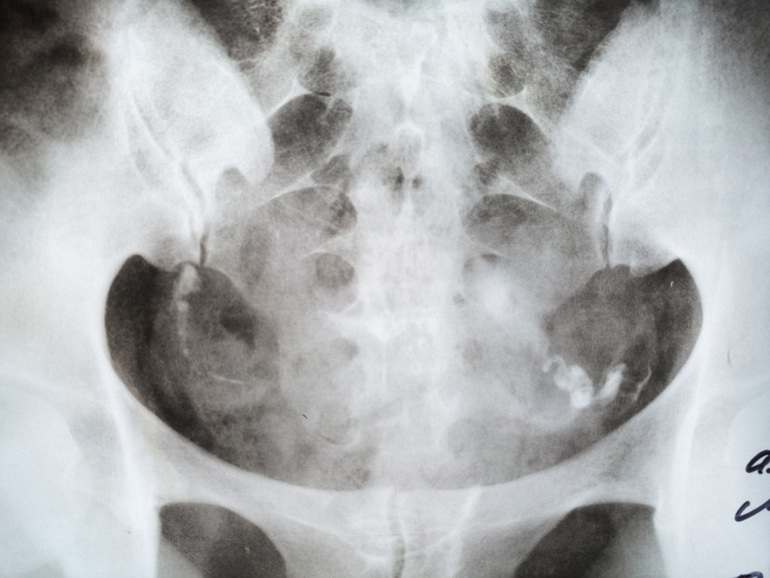

Проходимость труб. Нужно мнение.